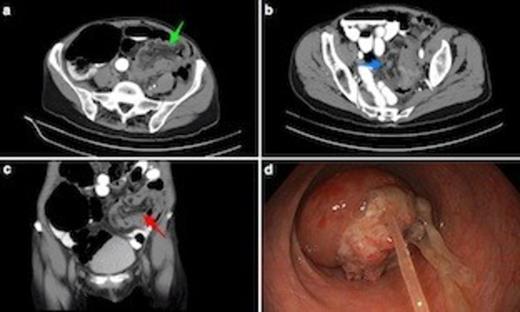

(a) Axial CT scan shows sigmoidorectal intussusception. Note bowel wall thickening. Low attenuation mesenteric tissue is drawn into intussusceptum, with associated caecal dilatation. (b) Axial view through mid-pelvis showing gas between bowel wall of intussusceptum and intussucipiens (i.e. sigmoid colon and rectum: this does not represent intramural gas). (c) Coronal view demonstrating mesenteric vasculature in the intussusceptum. (d) Endoscopic view from mid rectum of tumour intussusception. The underlying lesion was an apple core T3N1 adenocarcinoma of the mid-sigmoid. Note tumour mucus.

The patient proceeded to emergency surgery. On the operating table, flexible sigmoidoscopy confirmed the diagnosis of intussusception due to a sigmoidal tumour (Fig. 1d). At laparotomy, a mass in the mid sigmoid colon was found with intussusception of the tumour into the rectum. A Hartmann’s procedure was performed. Post-operative recovery was complicated by rapid atrial fibrillation, but was otherwise uneventful. The patient was discharged home nine days after surgery. Histopathology of the surgical specimen showed a T3N1 moderately differentiated colonic adenocarcinoma.